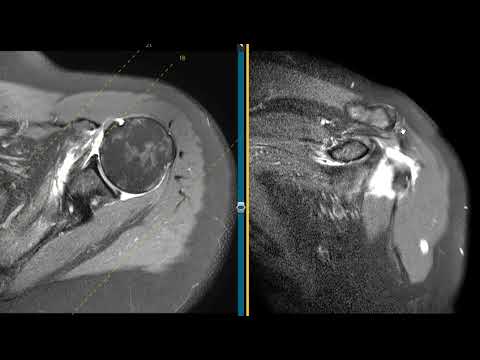

Массивный разрыв вращательной манжеты плеча у 58-летнего пациента